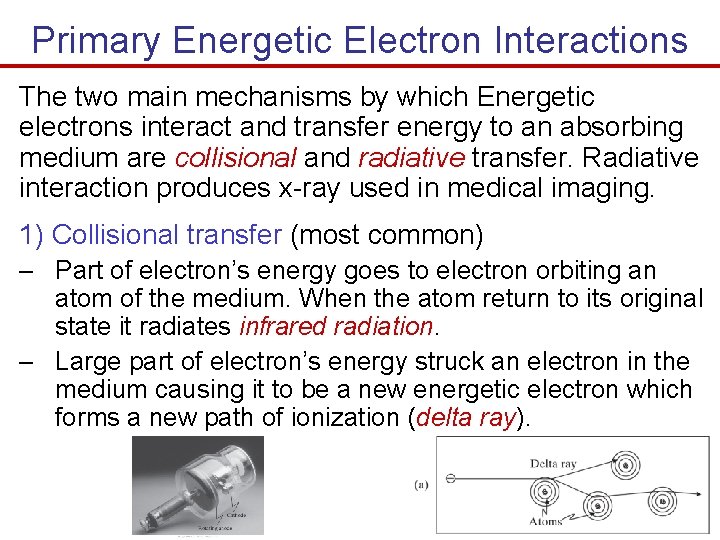

Primary Energetic Electron Interactions The two main mechanisms by which Energetic electrons interact and transfer energy to an absorbing medium are collisional and radiative transfer. Radiative interaction produces x-ray used in medical imaging. 1) Collisional transfer (most common) – Part of electron’s energy goes to electron orbiting an atom of the medium. When the atom return to its original state it radiates infrared radiation. – Large part of electron’s energy struck an electron in the medium causing it to be a new energetic electron which forms a new path of ionization (delta ray).